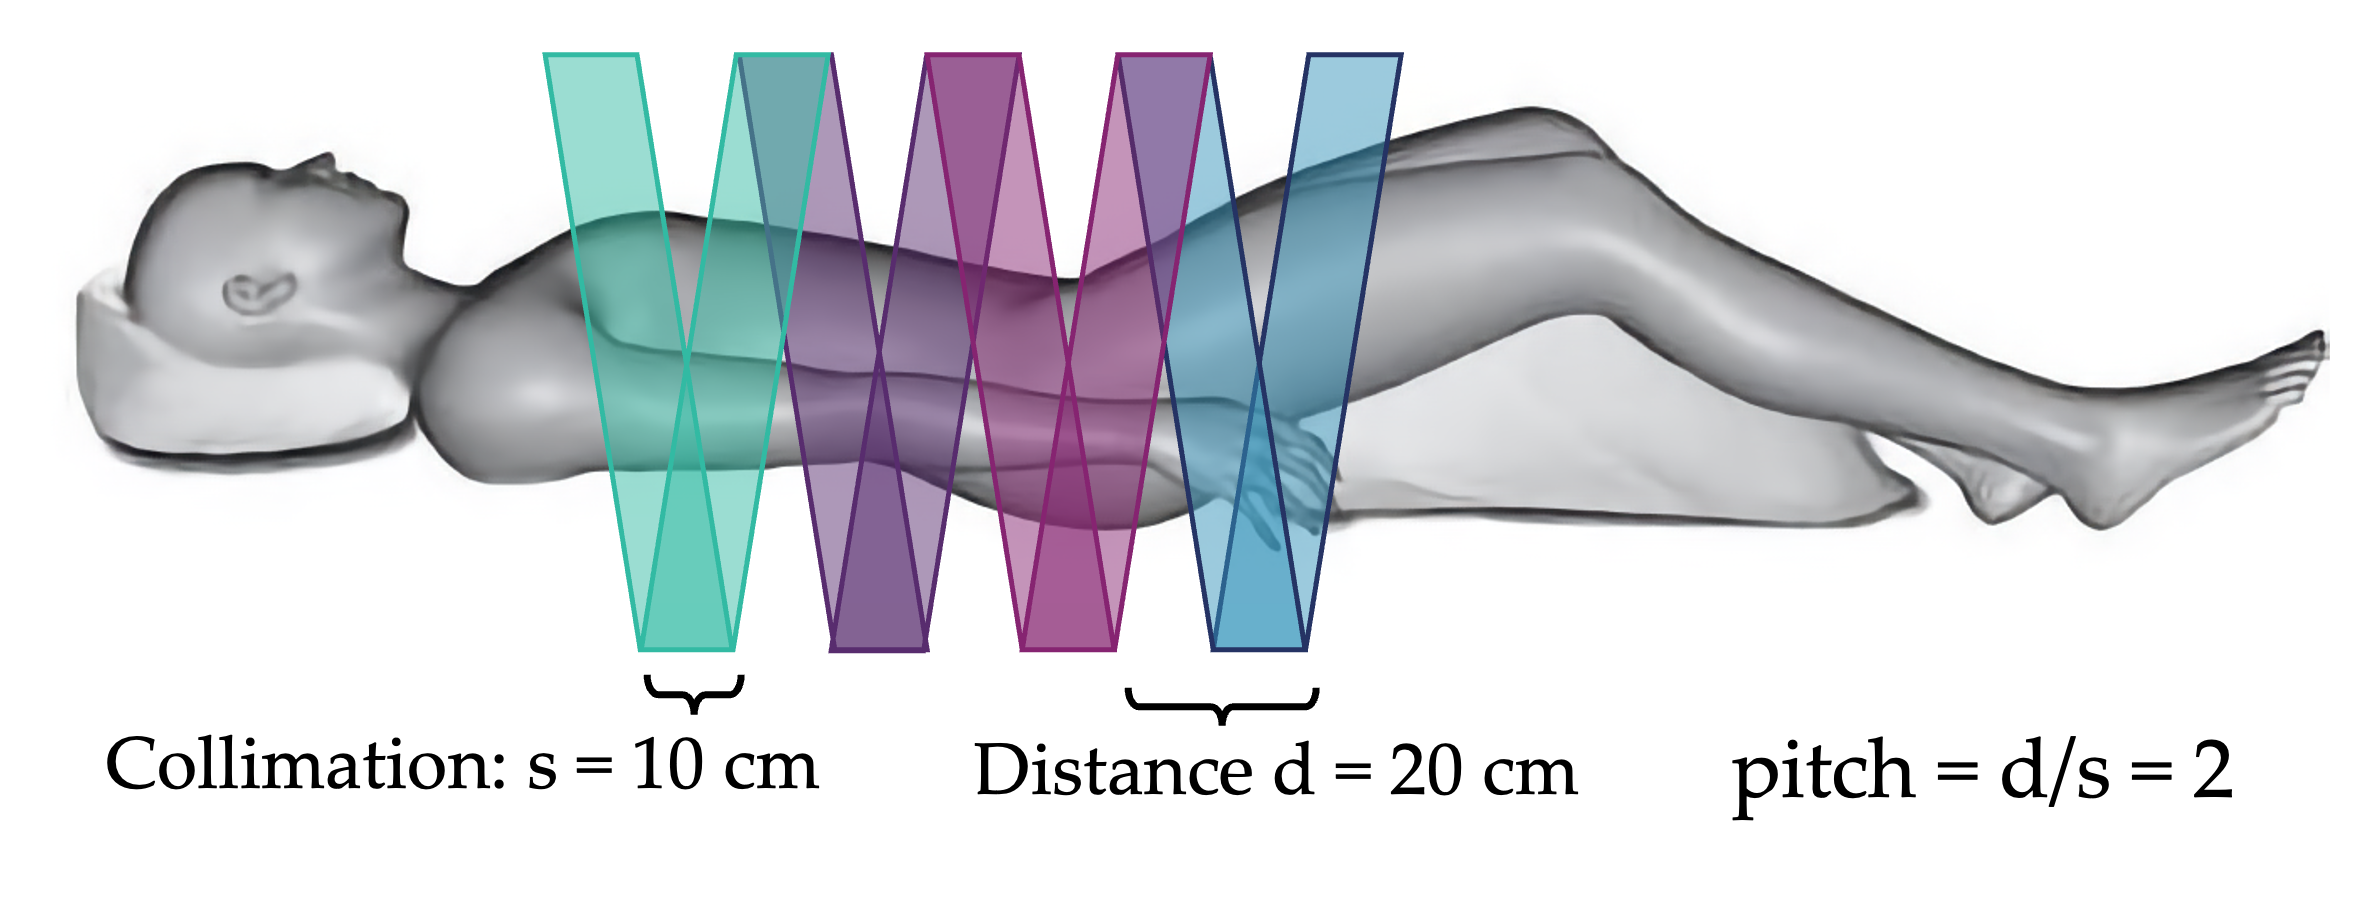

More commonly, modern CT scanners use a helical motion to acquire images. In this setup, the bed moves continuously while the tube-detector system rotate. This process results in faster imaging and greater dose control. The helical pitch determines the effective slice thickness and dose. Pitch is the distance the bed moves during one beam rotation, divided by the beam collimation. For overlapping motion, pitch is less than 1. Contiguous motion has pitch equal one, and extended motion has pitch greater than 1. The dose is roughly proportional to 1/pitch, such that higher pitches result in lower dose (less overlap). The final image slices are still axial and are reconstructed by averaging CT projections taken 180 degrees apart.

Question: if collimation is 10 cm and bed moves 20 cm per rotation, what is the pitch?

pitch = bed motion / collimation = 20 cm / 10 cm = 2 (extended)